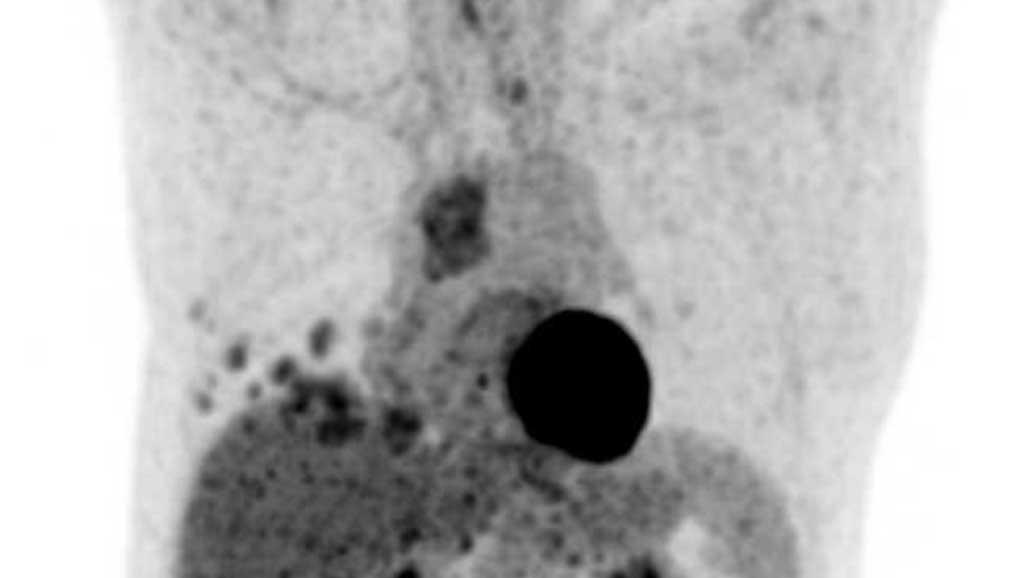

U lympho

Các hình ảnh này của một phụ nữ 34 tuổi có triệu chứng khó thở.

Hãy phân tích các hình ảnh.

Nhận định của bạn là gì?

Hình ảnh

Có một khối nang ở khoang trung thất trước mạch máu.

Thành nang dày và có ngấm thuốc cản quang.

Do vẫn chưa rõ bản chất tổn thương, PET scan đã được thực hiện.

Tiếp tục xem các hình ảnh PET…

Dựa trên kết quả PET, chẩn đoán nào là có khả năng nhất?

Đây là u tuyến ức dạng nang, nang biến chứng, u thần kinh nội tiết hay u lympho?

PET cho thấy nhiều tổn thương, đây phải là các hạch bạch huyết bệnh lý.

Thảo luận

U tuyến ức hầu như không bao giờ đi kèm với hạch to.

Nang bị nhiễm trùng cũng có thể gây hạch to, nhưng không lan rộng như trong trường hợp này.

Chẩn đoán cuối cùng

U lympho dạng nang.